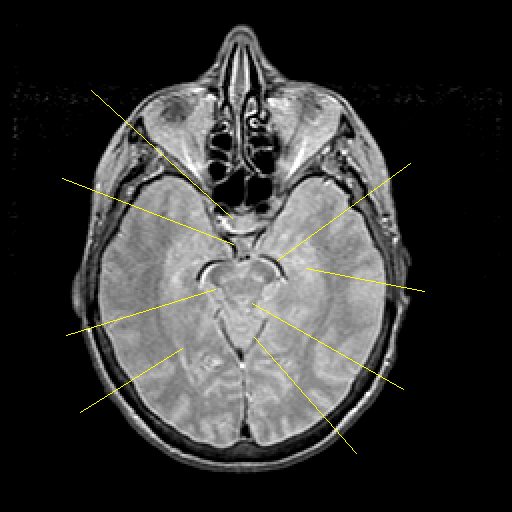

Proton density-weighted structural MR: Slice 21

Slice 21

Pointers

Labeled